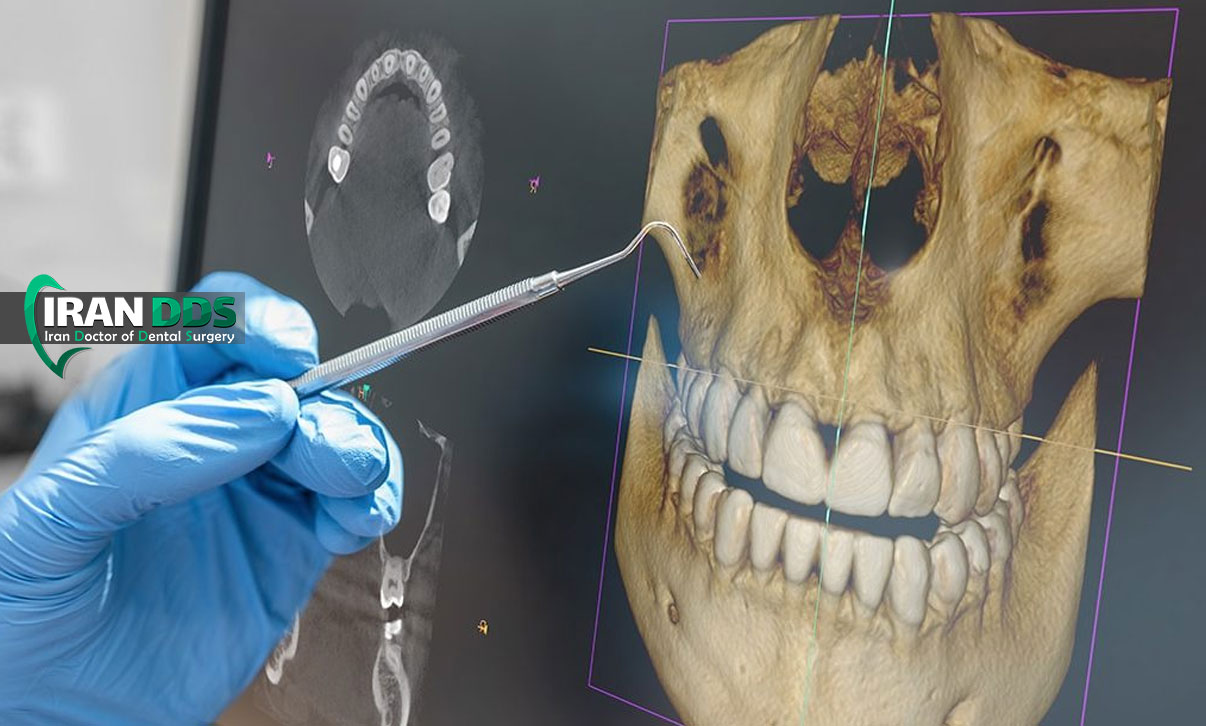

تصویربرداری سه بعدی در حوزه فک و صورت به مجموعه تکنولوژی هایی گفته می شود که امکان مشاهده ساختار های استخوانی، دندانی و در بعضی موارد بافت نرم را به صورت حجمی و سه بعدی فراهم می کنند. برخلاف رادیوگرافی های معمولی که یک تصویر تخت و دو بعدی از فک ارائه می دهند، در روش های سه بعدی می توان ساختار ها را از زوایای مختلف چرخاند، برش های سطحی و عمقی ایجاد کرد و اندازه گیری های بسیار دقیق تری انجام داد. مهم ترین فناوری سه بعدی در دندانپزشکی و جراحی فک، سی بی سی تی است که مخفف Cone Beam Computed Tomography می باشد. این روش با استفاده از یک پرتو مخروطی شکل اشعه ایکس، حجم کاملی از فک و صورت را اسکن و سپس با نرم افزار، مدل سه بعدی بازسازی می کند. برای جراح فک و صورت، این مدل مثل یک نقشه دقیق است که قبل از عمل، تمام جزئیات را نشان می دهد.

هدف از استفاده تصویربرداری سه بعدی فقط تهیه تصویر زیبا و واضح نیست، بلکه کمک به تصمیم گیری بهتر درمانی است. مثلا در بیمارانی که دچار جلو بودن بیش از حد فک پایین، عقب بودن فک بالا، عدم تقارن صورت یا مشکلات bite هستند، تصویر سه بعدی به پزشک کمک می کند محل دقیق مشکل را شناسایی کند، حجم جابه جایی استخوان را با دقت میلی متری محاسبه کند و حتی نتیجه جراحی را به صورت شبیه سازی شده به بیمار نشان دهد. از طرفی این فناوری در تشخیص موقعیت دقیق ریشه دندان ها، مسیر عصب آلوئولار تحتانی، ضایعات کیستیک و تومور ها، شکستگی های پیچیده و وضعیت راه هوایی نیز نقش مهمی دارد. بنابراین وقتی از نقش تصویربرداری سه بعدی در جراحی فک صحبت می کنیم، منظور یک ابزار مکمل و حیاتی در کنار معاینه بالینی، تست های دیگر و تجربه جراح است، نه جایگزین کامل آنها.

برنامه ریزی جراحی فک فرایندی بسیار دقیق و چند مرحله ای است که باید با همکاری نزدیک جراح فک و صورت، ارتودنتیست و گاهی متخصص خواب، گفتار درمانگر و جراح پلاستیک صورت انجام شود. تصویربرداری سه بعدی قلب این برنامه ریزی است. پس از تهیه سی بی سی تی، تصاویر به نرم افزار های تخصصی منتقل می شود و در آنجا جراح می تواند مدل سه بعدی فک ها را مشاهده، برش های مجازی ایجاد و حرکت های مختلف استخوان را شبیه سازی کند. این شبیه سازی شامل جابه جایی فک بالا و پایین در سه محور، چرخش ها، اصلاح عدم تقارن ها و حتی بررسی تاثیر این جابه جایی ها بر روی پروفایل صورت و لبخند است. به کمک این نرم افزار ها، جراح می تواند قبل از ورود به اتاق عمل، نسخه ای بسیار نزدیک به واقعیت از نتیجه را ببیند.

این نوع برنامه ریزی دیجیتال نه تنها دقت را بالا می برد، بلکه زمان جراحی را کوتاه تر و ریسک خطا را کاهش می دهد. علاوه بر این، از روی داده های سه بعدی می توان گاید های جراحی یا اسپلینت های راهنما چاپ سه بعدی کرد که در اتاق عمل مانند یک قالب دقیق روی دندان ها و فک بیمار قرار می گیرد و به جراح نشان می دهد فک ها دقیقا باید در چه موقعیتی فیکس شوند. این روش نسبت به روش های سنتی که بر اساس اندازه گیری های دستی و مدل های گچی بود، خطای بسیار کمتری دارد. همچنین امکان ذخیره سازی فایل ها و مقایسه قبل و بعد از جراحی وجود دارد که برای ارزیابی نتیجه، آموزش و حتی امور قانونی ارزشمند است. در نهایت، برنامه ریزی سه بعدی به جراح اجازه می دهد به صورت فرد محور و اختصاصی برای هر بیمار طرح درمان ویژه طراحی کند.